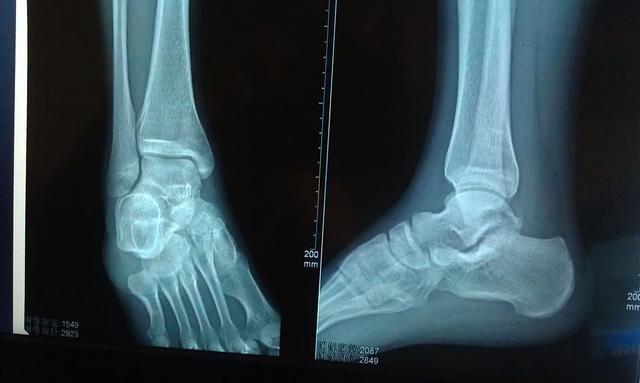

人在崎岖了道路上行走、奔跑或者上下楼梯时,很容易重心失衡,而导致脚忽然向内或向外翻转。而在崴脚后正确的处理方式是:首先判断脚崴之后是否伤及骨头。如果在扭伤以后,踝关节处肿胀并且行动受限,只能勉强走路,则是软组织扭伤。可如果在扭伤后,踝关节处出现明显畸形,并且伴有压痛感,则为踝关节骨折。